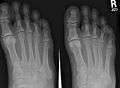

X-ray of foot, showing phalangeal fracture